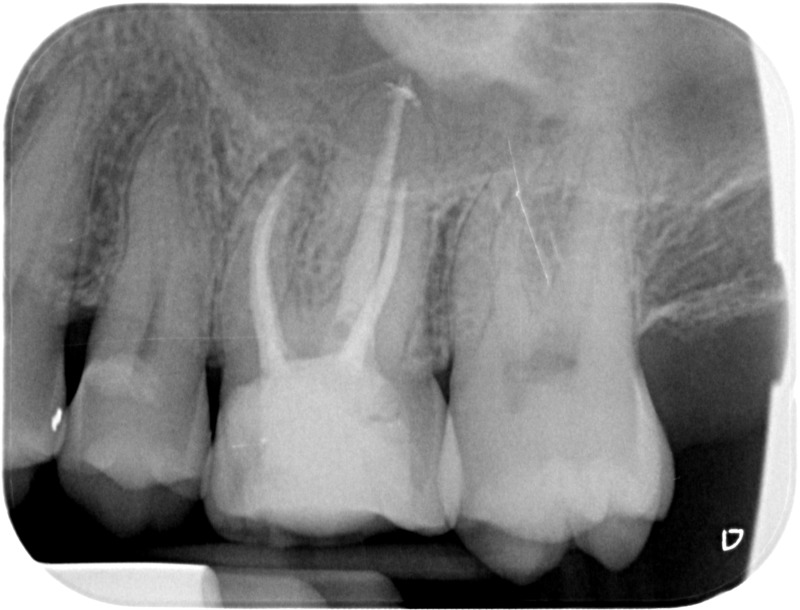

• Traitement endodontique : Sous anesthésie locale et à travers la protection d’un champ opératoire nous accédons à la pulpe de la dent à soigner, puis aux canaux de ses racines que nous devons désinfecter. Ce soin nécessite l’élimination complète de la source de contamination (souvent la carie) parfois sous une ancienne reconstitution ou une couronne qu’il faut alors retirer. Une fois le nettoyage et la mise en forme des canaux réalisés, nous les obturons de façon hermétique avec un ciment et un matériau thermoplastique appelé Gutta Percha. Ceci afin d’empêcher une nouvelle prolifération bactérienne et d’assurer le maintien de la dent dans ses structures de soutien (ligament parodontal et os alvéolaire). L’ouverture effectuée au centre de la dent sera d’abord refermée avec un pansement provisoire avant d’envisager ensemble la reconstitution d’usage : un composite, un inlay-onlay ou une couronne.

Après